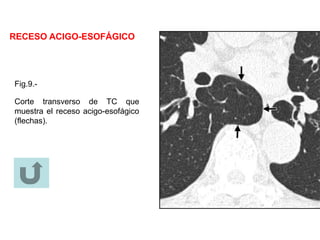

RECESO ACIGO-ESOFÁGICO

Anatomía.-

El receso acigo-esofágico es un receso mediastínico posterior derecho en el

que se expande el margen del lóbulo inferior derecho. Está limitado

superiormente por el cayado de la ácigos, posteriormente por la vena ácigos y

pleura anterior a la columna vertebral y medialmente por el esófago y

estructuras adyacentes.

Estudios con Rx y TC.-

En la RX frontal de tórax, el receso se ve como una interfase orientada

verticalmente entre el lóbulo inferior derecho y el mediastino adyacente (el

límite medial del receso). Superiormente, la interfase se ve como un arco liso

de convexidad izquierda. La desaparición o distorsión de parte de la interfase

sugiere enfermedad (ejemplo, adenopatia subcarinal). En los cortes de TC se

debe prestar atención al receso (fig.9), porque lesiones pequeñas en esa

localización a menudo son invisibles en la RX de tórax

Fig.9.-

Corte transverso de TC que

muestra el receso acigo-esofágico

(flechas).